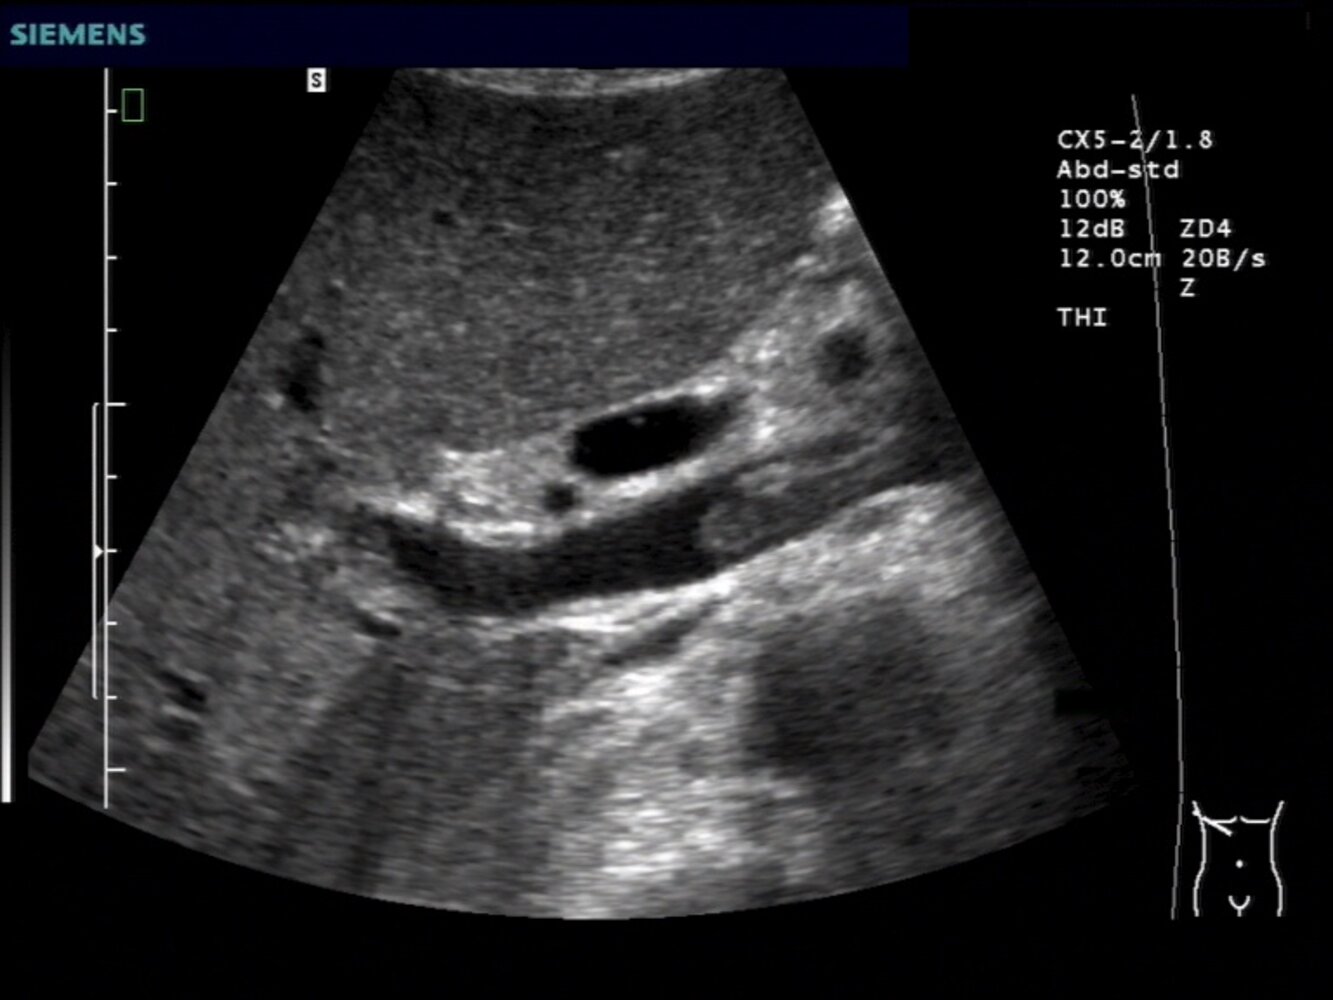

Abdominal ultrasound with Doppler: to assess liver damage [16]

-

Ultrasound findings

- Early: may include heterogeneous hypoechogenicity (sign of necrosis) and/or ascites

- Late: in patients who have been sick for at least seven days, may show a nodular surface, which can be mistaken for cirrhosis

- Doppler findings depend on the underlying cause, e.g., portal vein thrombosis, hepatic ischemia.